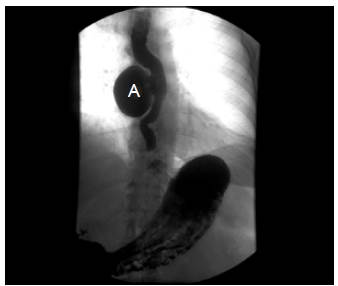

Mujer de 72 años de edad, con cuadro clínico de un año de disfagia y atragantamiento con alimentos sólidos, que había requerido tratamiento endoscópico. Se realiza endoscopia de vías digestivas altas que documenta un divertículo esofágico en tercio medio, y manometría esofágica de alta resolución, sin trastorno motor. El esofagograma (figura 1) y la tomografía computarizada de tórax (figura 2) muestran un divertículo en tercio medio de esófago, lateral derecho, de 7 cm de diámetro y base de 2.5 cm de diámetro. De manera programada se lleva a cabo diverticulectomía esofágica por toracoscopia, en decúbito prono (figura 3), sin complicaciones.